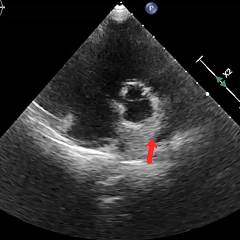

冠状动脉CTA:冠状动脉分布呈均衡型,左前降支中段浅肌桥;余冠状动脉CTA未见明显异常;卵圆孔未闭;左房囊袋。

冠脉CTA(长隧道+大开口+左房囊袋PFO)